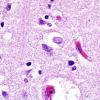

NEURODEGENERATION

Lewy Body Disease (LBD)

6 LBD - Microscopic Pathology - Cerebral Cortex (4)